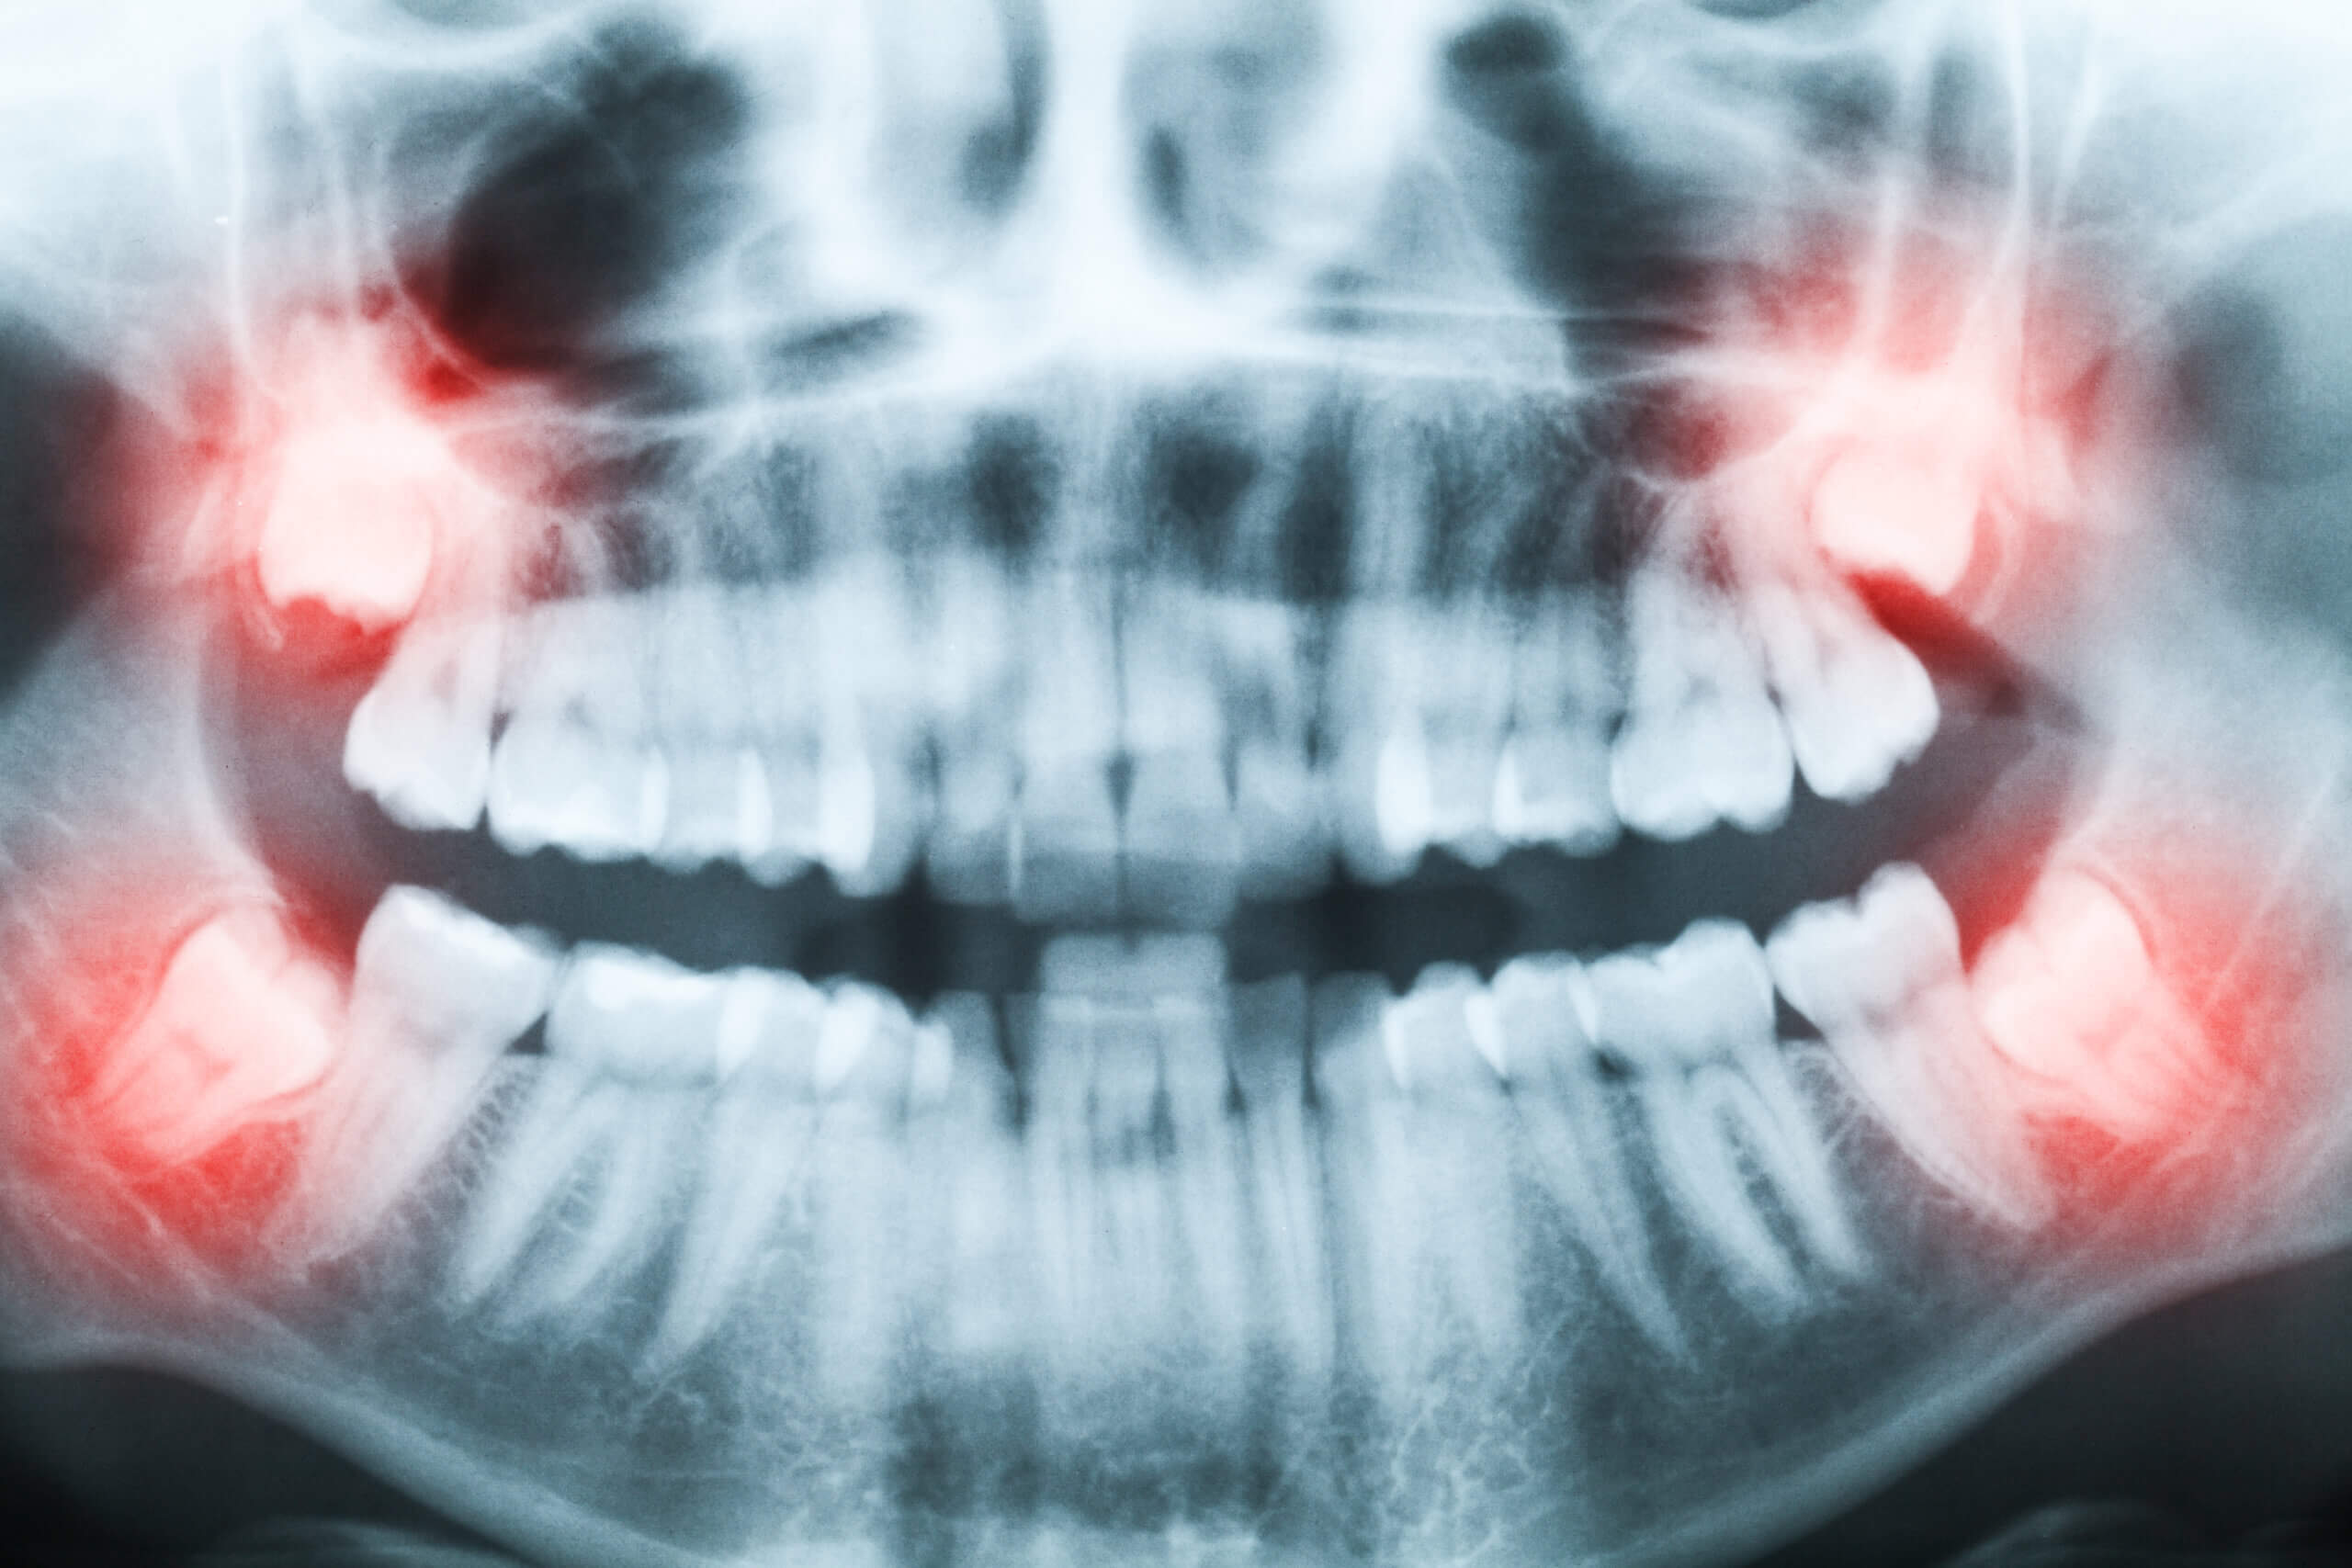

Having your wisdom teeth removed is a significant step toward safeguarding your long-term dental health and preventing future orthodontic issues that could affect your appearance. This proactive procedure helps prevent [...]

Grand Parkway Smiles is a multi-specialty dental implant, oral surgery, and general dentistry center in Katy, TX. Near Cinco Ranch. Our dental specialists have a combined 120+ years of experience including Dr. Ryan Smart oral surgeon, Dr. David Gomez dental implantologist, Dr. Louis Bosse prosthodontist, endodontist, and pediatric dentist—provides comprehensive, pain-controlled care under one roof. Services include dental implants, All-on-4 and snap-in dentures, wisdom teeth removal, root canals, extractions, full-mouth restoration, TMJ/TMD care, cosmetic dentistry, and IV sedation for anxiety or complex procedures. Same-day emergency visits available. We accept most PPO dental insurance and offer in-house payment plans and financing.